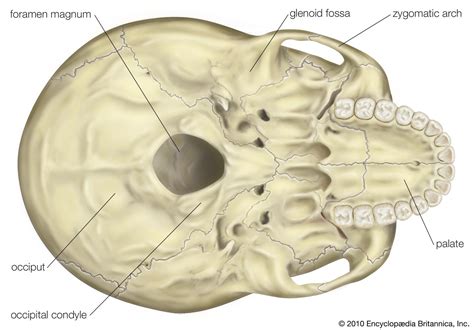

- Occipital Condyles: Located at the base of the skull, these condyles articulate with the atlas (first cervical vertebra) to form the atlanto-occipital joint, which allows for nodding movements of the head.